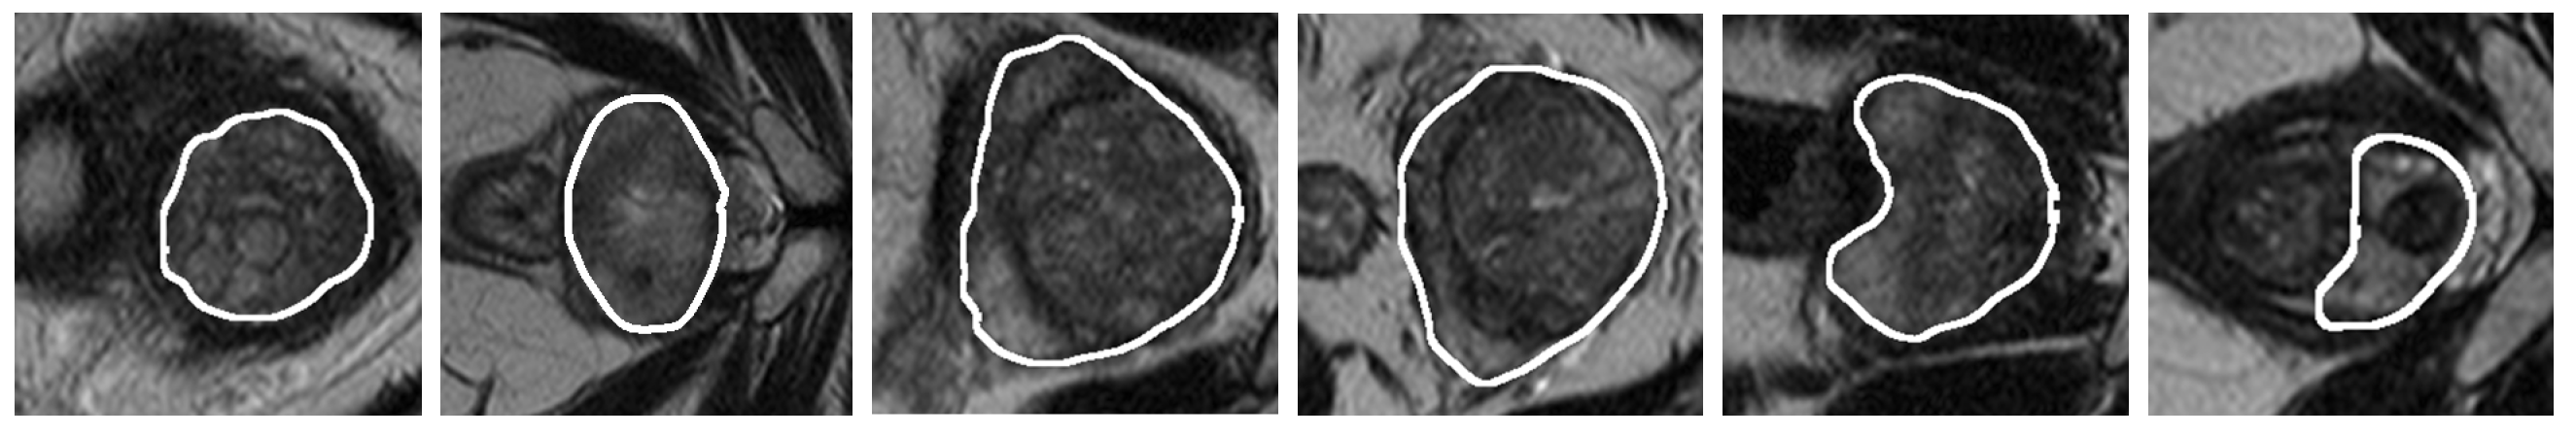

3. Validation of the Models

4. Results and Discussion